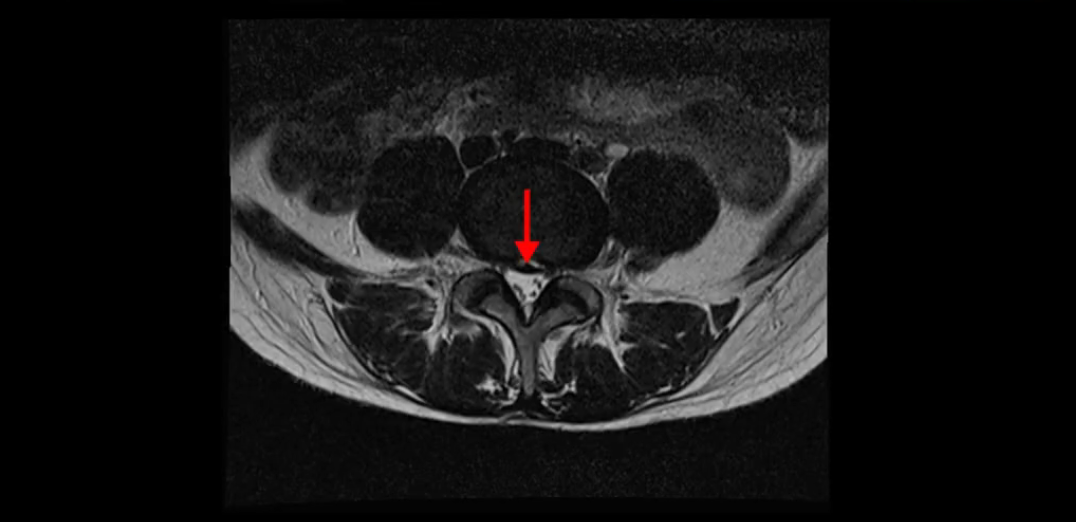

5번 1번은 디스크 탈출이 가운데 쪽으로 살짝 있습니다.

또한 양쪽 신경 가지가 빠져나가는 추간공은 매우 넓은 상태입니다.

중요한 것은 이 정도 경미한 탈출과 협착으로는 양쪽 다리가 저리고 아플 수가 없습니다.

그리고 만약에 이 디스크가 급성으로 찢어진 것이라면 아주 심한 디스크성 통증이 있겠죠. 기침이나 재채기를 하면 심하게 아프고 허리를 조금만 구부려도 아주 날카로운 통증들이 생길 겁니다. 그런데 이분은 이런 증상이 전혀 아닙니다. 디스크의 돌출 정도와 협착이 전혀 심하지 않기 때문에 이분이 가지고 계신 양쪽 다리 저림, 특히 이분은 누워있을 때도 양쪽 다리가 저리다고 하는데, 디스크 때문에 그런 증상은 생길 수가 없습니다. 또 이 디스크는 오래된 디스크, 이미 찢어진 섬유륜이 아문 디스크이고, 그러니까 이분은 기침이나 재채기를 못하는 증상이 없는 거죠. 그 다음에 허리를 구부릴 때 뻐근한 증상은 있지만 아주 날카로운 통증은 없습니다.

이분 MRI를 보시면 퇴행성디스크가 있고 약간의 협착이 있지만 이 정도의 퇴행성디스크와 협착으로는 신경이 눌려서 양쪽 다리가 저리고 아픈 증상이 나올 수가 없습니다. 그래서 MRI와 이 환자분의 다리 증상이 매치가 안 된다고 하는 의사들이 많은 겁니다.